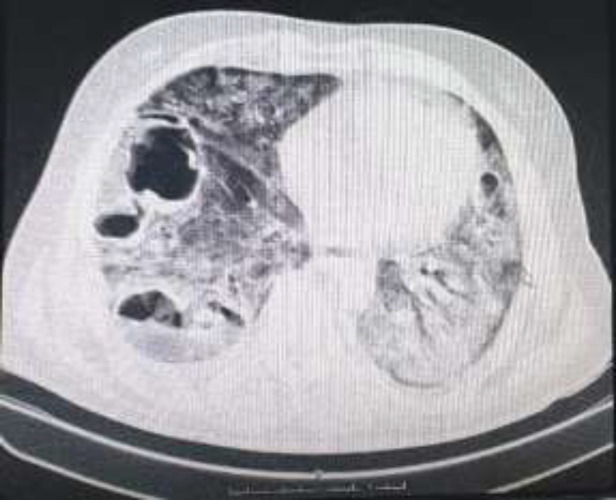

背景:我们的研究探讨了 COVID-19 后患者肺空洞的可能病因和特征。肺空洞是该病的晚期并发症,但它却导致多人转诊至我们位于伊朗德黑兰的三级医院:我们对 2020 年 4 月至 2021 年 9 月期间入住本中心的 20 名患者进行了回顾性病例系列研究。他们均被诊断为 COVID-19,并同时出现肺空洞。我们评估了他们在2021年的电子病历,并根据现有文献将他们的特征与其他研究进行了比较:结果:在 20 名龋齿患者中,12 人(60%)曾被诊断患有 COVID-19,9 人(45%)患有 2 型糖尿病。9名患者(45%)患有细菌性超级感染,4名患者(44%)患有真菌感染。所有患者都接受了皮质类固醇治疗,但只有4名患者(20%)额外使用了托珠单抗:结论:COVID-19 患者在康复期间可能会出现肺空洞,但这种不常见的放射学发现取决于特定的风险因素。

Background: Our study discusses the probable etiologies and characteristics of pulmonary cavities in post-COVID-19 patients. A pulmonary cavity is a late complication of the disease, yet it has led to multiple referrals to our tertiary hospital in Tehran, Iran.

Methods: We conducted a retrospective case-series study on 20 patients who were admitted to our center between April 2020 and September 2021. They were all diagnosed with COVID-19 and concomitantly developed pulmonary cavities. We assessed their electronic medical records in 2021 and compared their characteristics with other studies based on the available literature.

Result: Of the 20 patients with cavities, 12 (60%) had been diagnosed with prior COVID-19, and 9 (45%) had type 2 diabetes mellitus. 9 patients (45%) had bacterial superinfections while 4 (44%) had fungal infections. All patients received corticosteroids, but only 4 (20%) were additionally administered Tocilizumab.

Conclusion: COVID-19 patients can develop pulmonary cavities during recovery; however, this infrequent radiologic finding depends on specific risk factors.